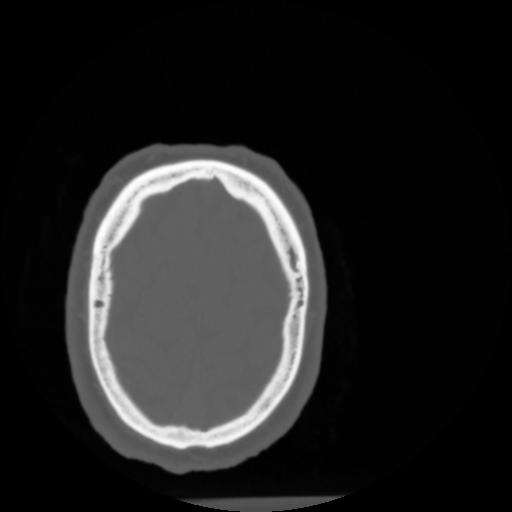

4 CEREBRO,,Vol,0.5,CEREBRO,,